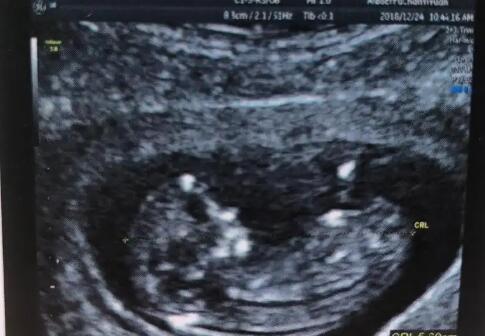

邯郸试管多少钱 2023邯郸妇幼保健院试管婴儿成功率: ‘b超查女孩儿准确率高吗’